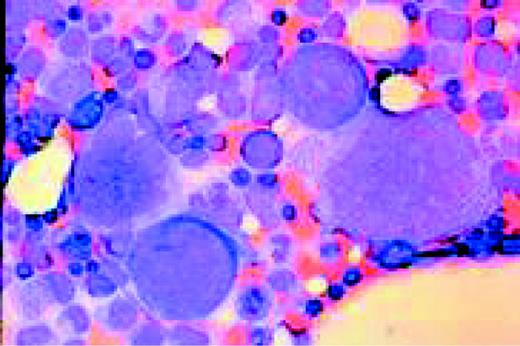

M7 Acute non-lymphoblastic leukemia (M7) (Acute megakaryocytic leukemia). This high-oil magnification view of a bone marrow aspirate shows the large blasts characteristic of this disease.FIG83

Slide MG2